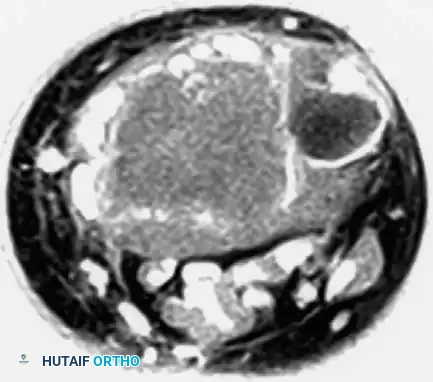

Advanced Imaging (MRI and CT)

Magnetic Resonance Imaging (MRI) is essential for evaluating the extent of the lesion, assessing articular cartilage integrity, and identifying secondary aneurysmal bone cysts (ABCs), which are present in up to 20% of patients. MRI typically reveals extensive bone marrow edema surrounding the lesion, which can be disproportionate to the tumor's size, further explaining the severe joint pain.

Computed Tomography (CT) is highly sensitive for detecting subtle intralesional calcifications and delineating the exact three-dimensional anatomy of the cortical margins, which is critical for planning the surgical approach and cortical window.